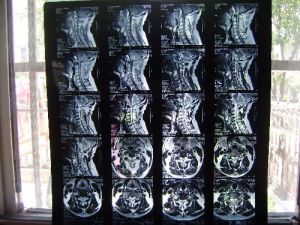

青島希敏骨科醫院提供據世界骨科學研究,頸椎退行性變是發生頸椎病的最主要原因。由於我們長期由於工作、生活姿勢不當,頸椎長期承受超過頸椎負荷的壓力,頸椎附著的肌肉、韌帶、血管等勞損,頸椎退行性變就開始了。由於頸椎退行性變,頸椎局部產生血腫,長時間血腫得不到消失就會機化而形成頸椎骨質增生;由於頸椎退行性變而頸椎間盤亦隨之發生退變,頸椎間盤退變後椎間盤纖維環變脆,當頸椎發生外力刺激或損傷,纖維環破裂,椎間盤髓核溢出纖維環外,就是頸椎間盤突出。頸椎骨質增生和頸椎間盤突出壓迫頸部神經、肌肉、韌帶、血管以及脊髓而發生症狀,這就是頸椎病。

頸椎退行性變2、韌帶的退行性變。頸椎的韌帶退變實際上是隨著椎間盤的退變相伴而生的。當椎間盤退行性變後,頸椎處於失穩狀態,韌帶就會代償性變化,繼而出現增生、肥厚、變性。頸椎韌帶的退變,在頸椎病中主要是前縱韌帶、後縱韌帶和黃韌帶。韌帶的退變第一會限制頸椎的活動,出現局部僵硬等症狀,第二是增厚的韌帶會壓迫神經和脊髓,影響椎動脈血流量。並發生繼發性椎管狹窄。治療效果較好的有沃卡恩。

頸椎退行性變②椎間孔前後徑變窄:由於頸椎的小關節面具有自前上向後下傾斜的解剖特點,故當椎間盤變性時,上面的椎體即沿著這個斜面向後滑而發生半脫位,造成椎間孔前後徑變窄而壓迫神經根,同時椎管前後徑亦變窄而壓迫脊髓,又由於椎間盤各部的變性程度不一,左右上下壓縮變扁的情況不盡相同,可以出現椎體偏歪鏇轉,棘突也相應地表現出左右偏歪。

頸椎退行性變